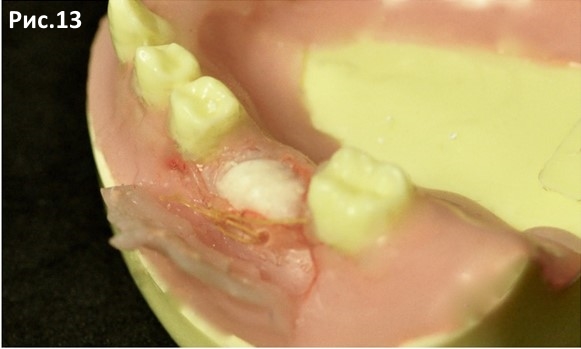

Заправляем край коллагеновой мембраны под язычный лоскут, предотвращая тем самым миграцию материала. Рис.13